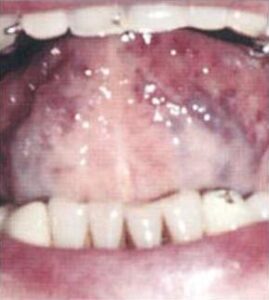

Dil üzerindeki mukoza sürekli yenilenir. Şayet kişi sürekli besini sıvı olarak alırsa veya fazla çiğnemeden yutarsa ölü hücreler, yemek artıkları ve mikro organizmalardan dil üzerinde pas gibi beyaz bir tabaka oluşur. Sert ve katı besinler ise dili üzerini temizler ve bir ilaç gibidir. Dil üzerindeki beyazımsı tabaka ağız Mantarı olabilir. Ateşli bir enfeksiyon, gastrit veya sifilis gibi bir hastalığın dilde yansıması olabilir. Dil iltihaplanması ise kaygan, kırmızı ve dilde yanma gibi bir acı ile kendini gösterir, yani dil iltihaplanması farklıdır. Çok nadiren aşırı alkol, sigara ve başka kanserojen madde kullananların dilinde kötü huylu urlar olabilir.

Maya mantarları:

Sabahları dil üzerinde beyaz bir tabaka görülmesi gayet normaldir ve paniğe gerek yoktur, çünkü gece vücudun kendi hücreleri veya yabancı maddeler dil üzerinde toplanır. Fakat bu beyaz tabaka sürekli çoğalıyorsa o zaman maya Mantarı var demektir. Maya mantarları mide ve bağırsaklara yerleşir, bağışıklık sitemi güçlü ise bu Mantarı yok eder. Fakat bazı kimyasal ilaçlar özelliklede antibiyotikler sindirim sistemindeki faydalı bakterilerin azalıp zararlı bakteri ve mantarların çoğalmasına sebep olur. Mantar tatlı yiyecek ve içeceklerle normalden 200 kat hızla çoğalır. Bu nedenle bağırsaklarında Mantar olanların kesinlikle tatlı yememeleri ve hamurlu yiyecekleri azaltmaları gerekir. Eğer yanlış beslenilirse zamanla bağışıklık sistemi mantarları yenemez ve mantarlar toksik maddeler üreterek birçok hastalığı tetiklerler.

1-) Beyaz dil pası genellikle gastrit, enteririt, kolit, gastoenterit gibi mide ve bağırsak enfeksiyonuna işarettir. Mide ve bağırsaklarda çok yoğun bakteri ve Mantar olduğunu gösterir.